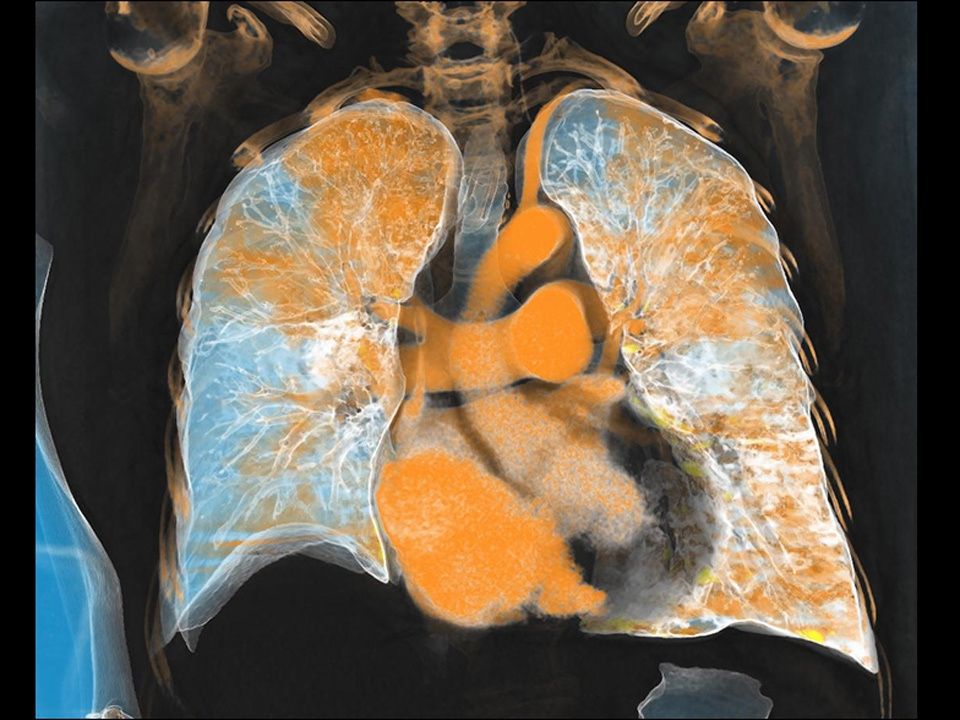

CT DE Lung Analysis

Assessment of perfusion defects and affected vessels at a glance.